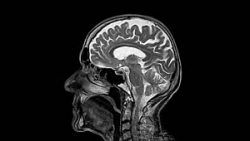

Eine mögliche Ursache des sogenannten "kalorischen", d.h. durch Temperaturunterschiede bedingten, Schwindels ist in der Grafik 22 dargestellt.

Kommt es bei einem Mittelohr-Barotrauma zum Einriss des Trommelfells und damit zum Eintritt von kaltem Wasser in das Mittelohr, so führt das kalte Wasser zu einer vorübergehenden Abkühlung im Bereich des Mittelohres.

Da der seitliche Bogengang des Gleichgewichtsorgans nur durch einen dünnen Knochen vom Mittelohr getrennt ist, kommt es hier auch zu einer Abkühlung der Innenohrflüssigkeit im Bogengang.

Die abgekühlte, physikalisch schwerere Innenohrflüssigkeit sinkt ab und führt so zu einer Flüssigkeitsbewegung im seitlichen Bogengang, die von Nervensystem als Drehbewegung des Körpers interpretiert wird.

Nach Erwärmung des eingedrungenen Wassers verschwindet der Drehschwindel jedoch wieder innerhalb weniger Minuten.